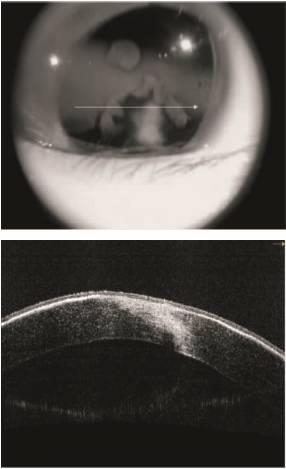

患者,男,7岁,1年半前因左眼被笤帚击伤,诊断为:左眼穿通伤,外伤性白内障,视网膜脱离,于当地医院分别行左眼外伤缝合术,晶状体切割、玻璃体切割视网膜手术联合硅油填充术,硅油取出术,玻璃体切割联合硅油填充术等4次手术。于2014年12月25日来我院眼科就诊,眼科检查:左眼视力眼前手动,眼压 7 mmHg(1 mmHg=0.133 kPa),角膜睑裂部橫行带状白色变性区,约 9 mm×5 mm(见图 1),前房硅油填充,晶状体缺如,隐约见视网膜裂孔及脱离。左眼角膜地形图显示 K1 47.36 D×105°,K2 43.48 D×15°(见图 2)。光学相干断层扫描(OCT)示左眼角膜中央厚度约 590 μm,最薄点厚度约 527 μm,角膜变性区厚度位于角膜前表面约 100 μm 范围内(见图 3)。

左眼角膜睑裂部约 9 mm×5 mm 带状白色变性区

图 1 左眼角膜带状变性患者眼前节裂隙灯显微镜下所见

角膜中央厚度约 590 μm,最薄点厚度约 527 μm,角膜变性区厚度位于角膜前表面约 100 μm 范围内

图 3 左眼角膜带状变性患者眼前节 OCT 图像